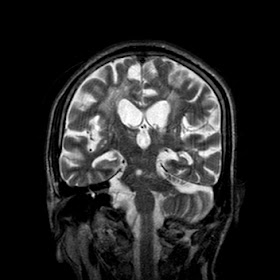

A 55 years old man with....